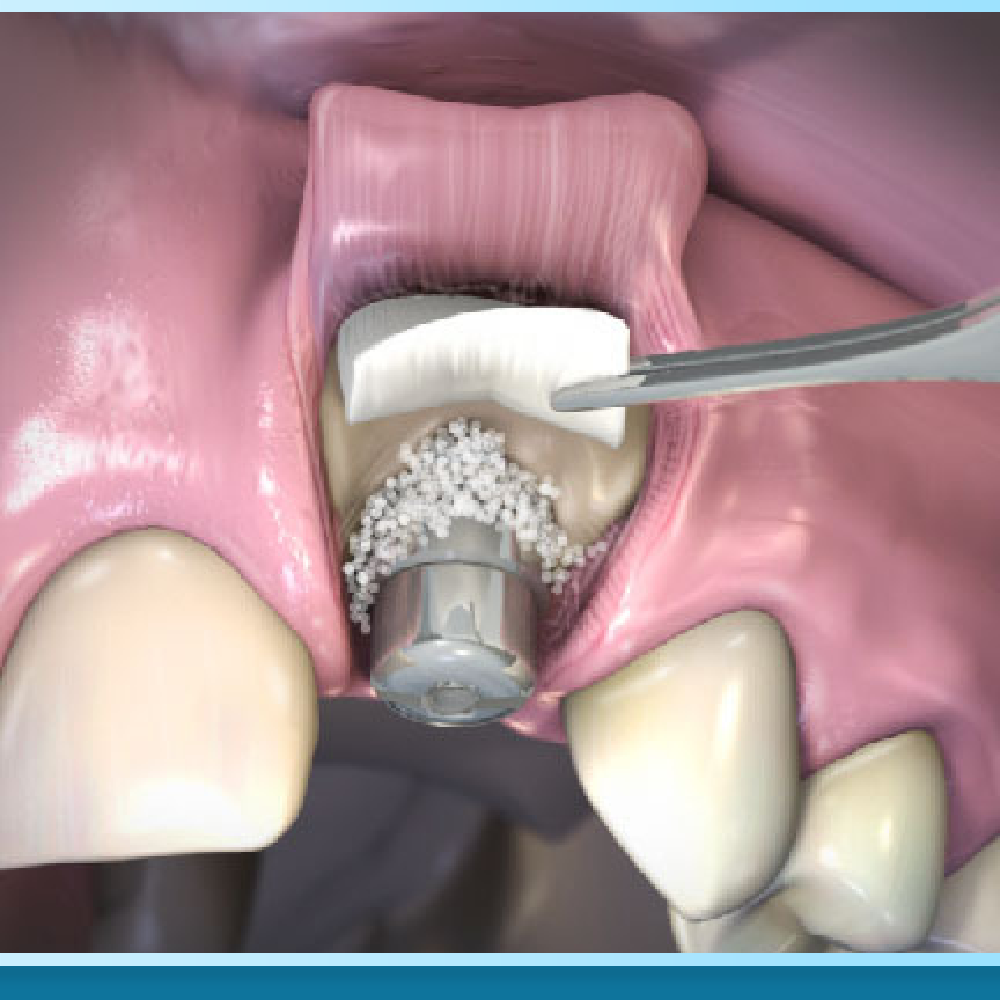

Đầu tiên là chi phí Ghép xương (Bone Grafting). Đối với những người mất răng lâu năm, xương hàm thường bị tiêu biến, trở nên mỏng và xốp. Để trụ Implant có thể đứng vững, bác sĩ buộc phải ghép thêm bột xương nhân tạo hoặc xương tự thân để tái tạo nền móng. Chi phí này thường được tính theo đơn vị răng hoặc trọng lượng (gram) bột xương sử dụng, dao động từ vài triệu đồng cho một vị trí.

Đi kèm với ghép xương là chi phí Màng xương (Membrane). Đây là một lớp màng sinh học (thường là Collagen) được đặt phủ lên trên bột xương ghép. Nhiệm vụ của nó là che chắn, cố định bột xương không bị trôi và ngăn mô mềm xâm lấn vào vùng ghép xương. Thông thường, chi phí màng xương sẽ được tính riêng hoặc đi kèm trong gói ghép xương tùy quy định của từng nha khoa.